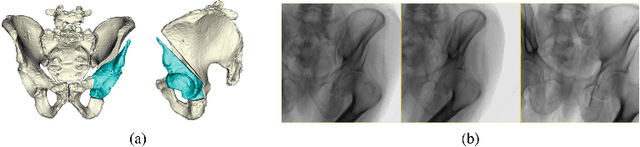

Periacetabular osteotomy is a challenging surgical procedure for treating developmental hip dysplasia, providing greater coverage of the femoral head via relocation of a patient's acetabulum. Since fluoroscopic imaging is frequently used in the surgical workflow, computer-assisted X-Ray navigation of osteotomes and the relocated acetabular fragment should be feasible. We use intensity-based 2D/3D registration to estimate the pelvis pose with respect to fluoroscopic images, recover relative poses of multiple views, and triangulate landmarks which may be used for navigation. Existing similarity metrics are unable to consistently account for the inherent mismatch between the preoperative intact pelvis, and the intraoperative reality of a fractured pelvis. To mitigate the effect of this mismatch, we continuously estimate the relevance of each pixel to solving the registration and use these values as weightings in a patch-based similarity metric. Limiting computation to randomly selected subsets of patches results in faster runtimes than existing patch-based methods. A simulation study was conducted with random fragment shapes, relocations, and fluoroscopic views, and the proposed method achieved a 1.7 mm mean triangulation error over all landmarks, compared to mean errors of 3 mm and 2.8 mm for the non-patched and image-intensity-variance-weighted patch similarity metrics, respectively.